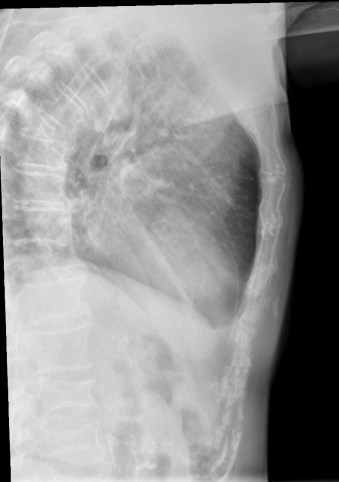

CASO: Febrícula y tos de 4 días de evolución.

Hallazgos:

- En la placa PA se observa una asimetría en los hilios pulmonares, el hilio izquierdo tiene una densidad aumentada.

- Tras examinar la placa lateral se observa un aumento de densidad en la columna que puede ser compatible con una condensación, es el signo de la desnificación vertebral.

SIGNO DE LA DENSIFICACIÓN VERTEBRAL: En la radiografía lateral normal, la densidad de la columna torácica tiende a disminuir desde la parte superior hasta el diafragma; la alteración de ese patrón por la presencia de una densidad superpuesta a la columna, indica la existencia de una consolidación pulmonar. Este signo adquiere especial valor cuando en la proyección posteroanterior la consolidación está oculta en el espacio retrocardíaco o en la base pulmonar.